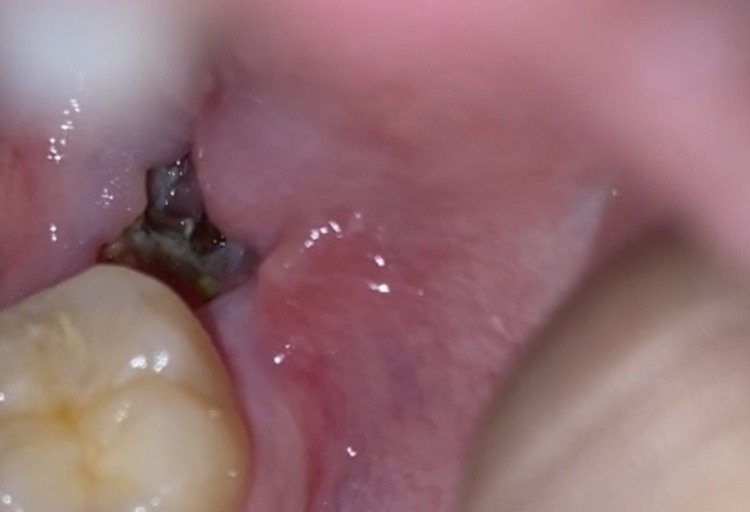

Is this normal healing of extraction sites

I had 2 wisdom and 2 molars removed as of now 5 days ago and these photos were taken on day 3, I was concerned that they may be infected, but there is no pain or outrageous swelling, no bleeding either and I can't really tell if there is a bad smell...

Wisdom teeth removed, is this dry socket or healing normally?

I’m concerned I have a dry socket from my salt rinses. Does this look like normal healing or is something wrong? It has a gray color and on the right side I can see some white. I got my teeth removed on 5/3 and felt like I was healing alright. I got...